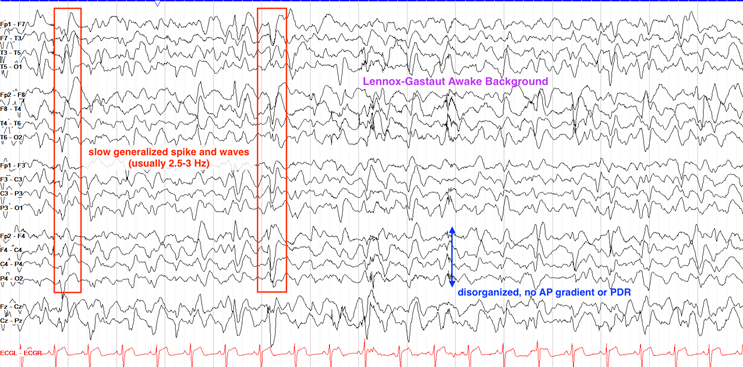

Lennox-Gastaut 综合征(LGS) | 1–8岁 | 慢棘慢波(1.5–2.5 Hz)、全面性快棘波(10–20 Hz),睡眠期增强。 |

Lennox-Gastaut综合征